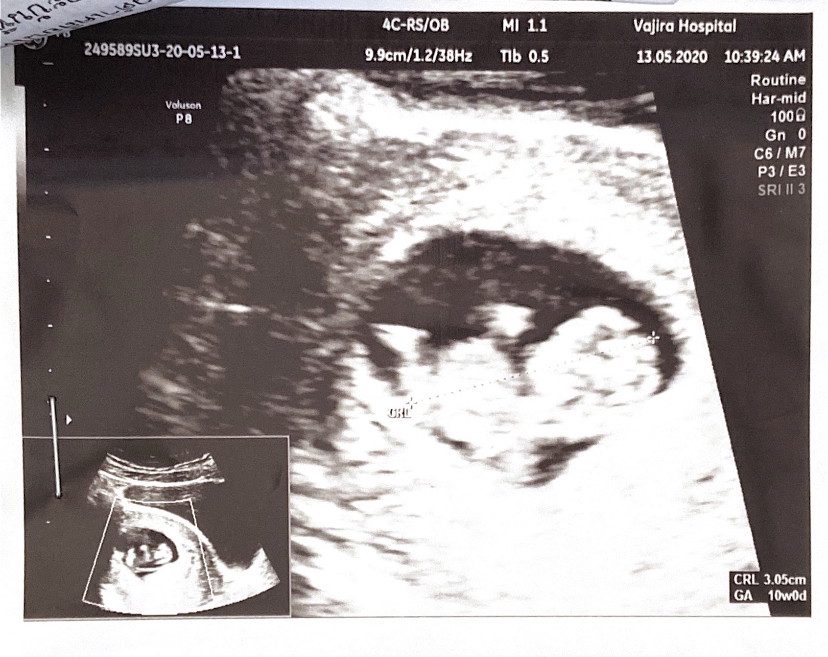

6 ธ.ค. 63 ค่ะ | ซาวด์ตอน 10w 3d